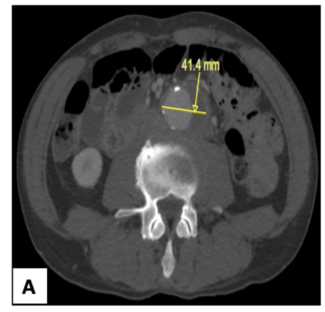

The case study discusses diagnosis and management features of abdominal aortic aneurysms due to Campylobacter fetus bacteremia.